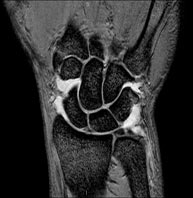

- Knee MRI

Examination to study joint injuries, such as meniscal tears and cruciate ligament tears (only detectable through this test), chondropathy or cartilage wear, and a multitude of other disorders resulting from sports activities and degenerative changes (osteoarthritis). It lasts approximately 18 minutes. It is a radiation-free procedure.